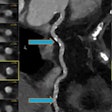

EVT promising in patients with extracranial ICA occlusions